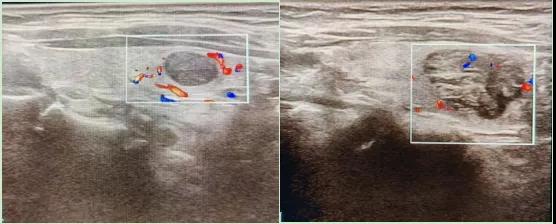

二、彩超如何“揪出”甲狀腺瘤?

彩超是一種無創(chuàng)、無輻射的檢查手段,被譽(yù)為甲狀腺的“高清攝像頭”。它的原理是:

超聲波探測(cè):通過發(fā)射高頻聲波,生成甲狀腺的實(shí)時(shí)圖像。

彩色血流顯示:用紅藍(lán)色標(biāo)記血流信號(hào),區(qū)分腫瘤的供血情況。

三、彩超報(bào)告里的“暗語”解讀

醫(yī)生會(huì)通過以下特征判斷腫瘤性質(zhì):

1.形態(tài):良性多呈圓形,邊界清晰;惡性可能不規(guī)則、邊緣模糊。

2.回聲:低回聲結(jié)節(jié)風(fēng)險(xiǎn)較高(像“烏云”一樣暗)。

3.鈣化:細(xì)小砂礫樣鈣化提示惡性可能。

4.血流信號(hào):惡性結(jié)節(jié)常有豐富紊亂的血流。